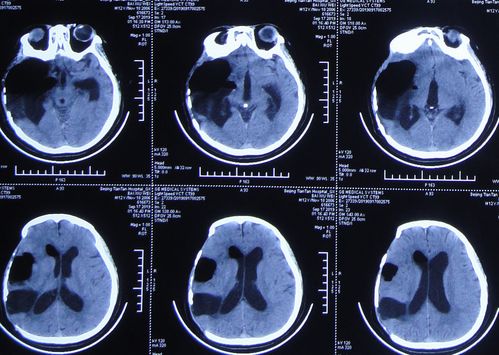

对于疑似第四脑室占位合并脑积水的患者,神经影像学检查是诊断和评估的金标准。

计算机断层扫描(CT):可快速显示脑室系统(尤其是侧脑室和第三脑室)的对称性扩张,提示梗阻性脑积水。CT也能较好地显示肿瘤内的钙化(室管膜瘤常见点状或斑片状钙化)以及急性出血^。

通过影像学,医生不仅能明确第四脑室占位的性质和范围,还能精确判断梗阻性脑积水的程度、脑室扩张的模式以及是否存在脑疝等紧急情况,为制定治疗方案提供决定性依据^。